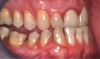

Fig 18. Bite interdigitation to finalize surgical orthodontic correction. After orthodontics, periodontal plastic surgery, bleaching, microabrasion, and restorative dentistry were performed.

Fig 19. Bite interdigitation to finalize surgical orthodontic correction. After orthodontics, periodontal plastic surgery, bleaching, microabrasion, and restorative dentistry were performed.

Fig 20. Bite interdigitation to finalize surgical orthodontic correction. After orthodontics, periodontal plastic surgery, bleaching, microabrasion, and restorative dentistry were performed.